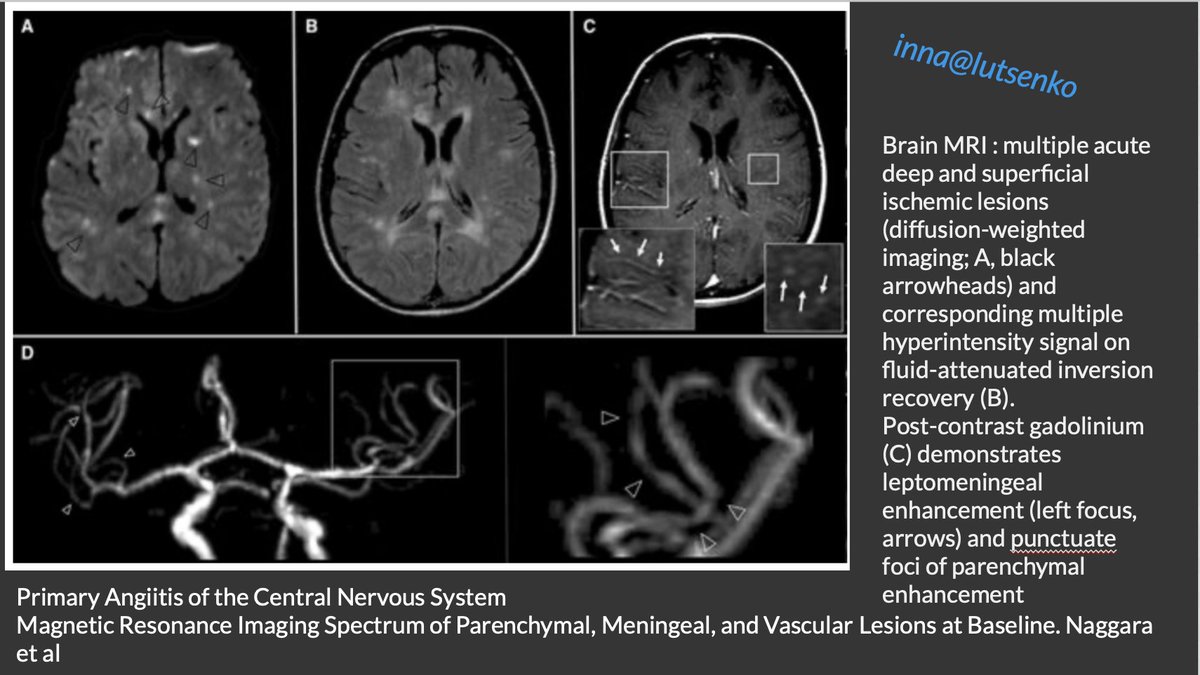

@ESOstroke #PACNS #NEUROIMAGING

#Brain #MRI :

➡️multiple acute deep and superficial #ischemic lesions (DWI)

➡️corresponding multiple hyperintensity signal on #FLAIR

➡️Post-contrast #gadolinium: leptomeningeal enhancement

@ESOstroke #neurotwitter

10/